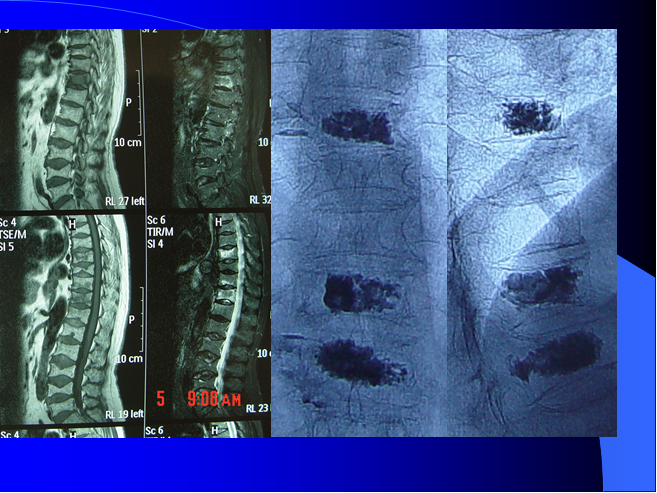

马燕萍 神经外科 护士长